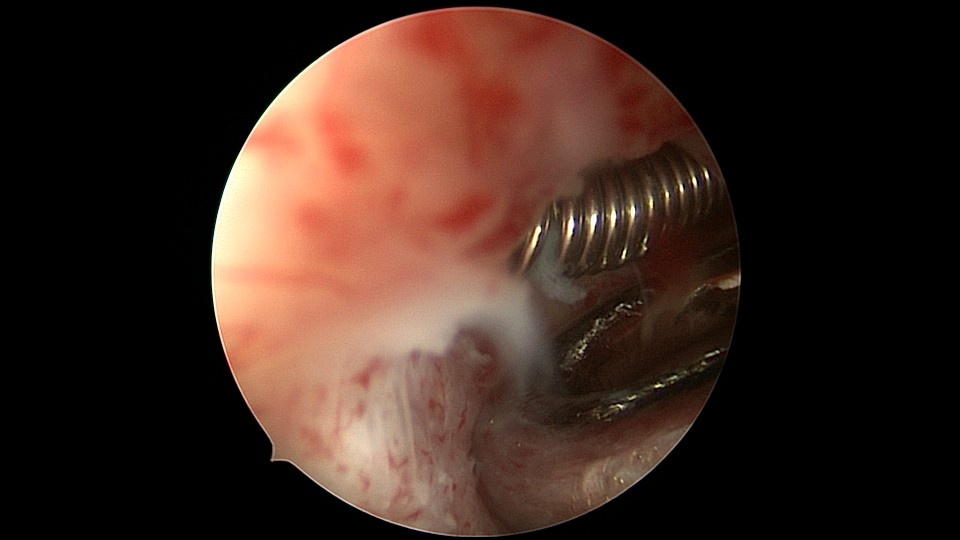

患者54岁,G1P1,剖宫产1次,安环30+年,绝经4年。40年前患者曾行左侧髋关节骨折手术,左下肢外展困难,患者肥胖,阴道很深,金属扩阴器和一次性扩阴器均无法暴露宫颈,用阴道内镜方式进入宫腔,但宫腔镜长度不够,远远能看见环,无法到达环的部位,再次试图暴露宫颈失败,用宫颈钳夹着阴道壁下拉,宫腔镜进入宫腔,但异物钳夹持力度不够,取出失败。用取环钩盲探沿宫腔镜外侧推挤进入宫腔,经历多次拧转,取环钩几乎向前弯成直角,直视下终于钩住节育环,掰直取环钩后缓慢拉出节育环,环变形。